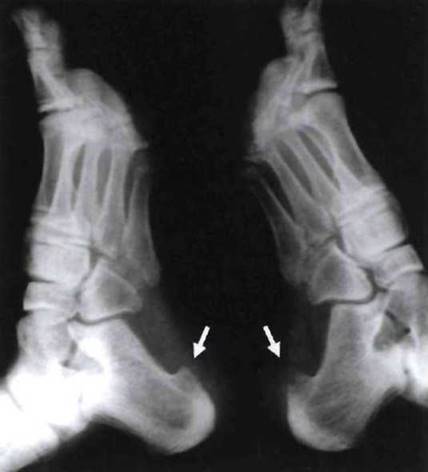

Рис. 23-11, Остеофиты в месте фиксации плантарной фасции к нижним краям пяточных бугров (указано стрелками) у больного ЮАС.